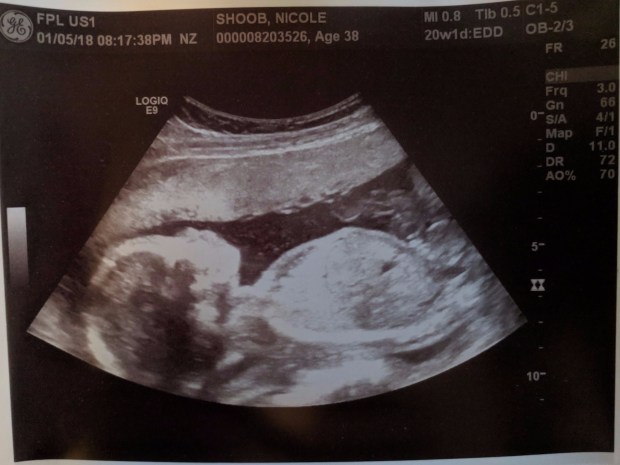

We got great news the other night. At our 20 week anatomical survey they were able to tell us that our little baby is a boy! It was just the imaging technician working so there will be a doctor that follows up after they review all the scans. But as far as Nicole and I can tell he looks just like a baby. It was so cool to be able to see little hands and feet. Right now the estimated weight is 12 oz so about the size of a bag of coffee.